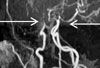

MRI is now central to the diagnosis of multiple sclerosis. Because of the modality’s high sensitivity to inflammation and demyelinating plaques, roughly 90% of all MS diagnoses are now based on MRI findings.